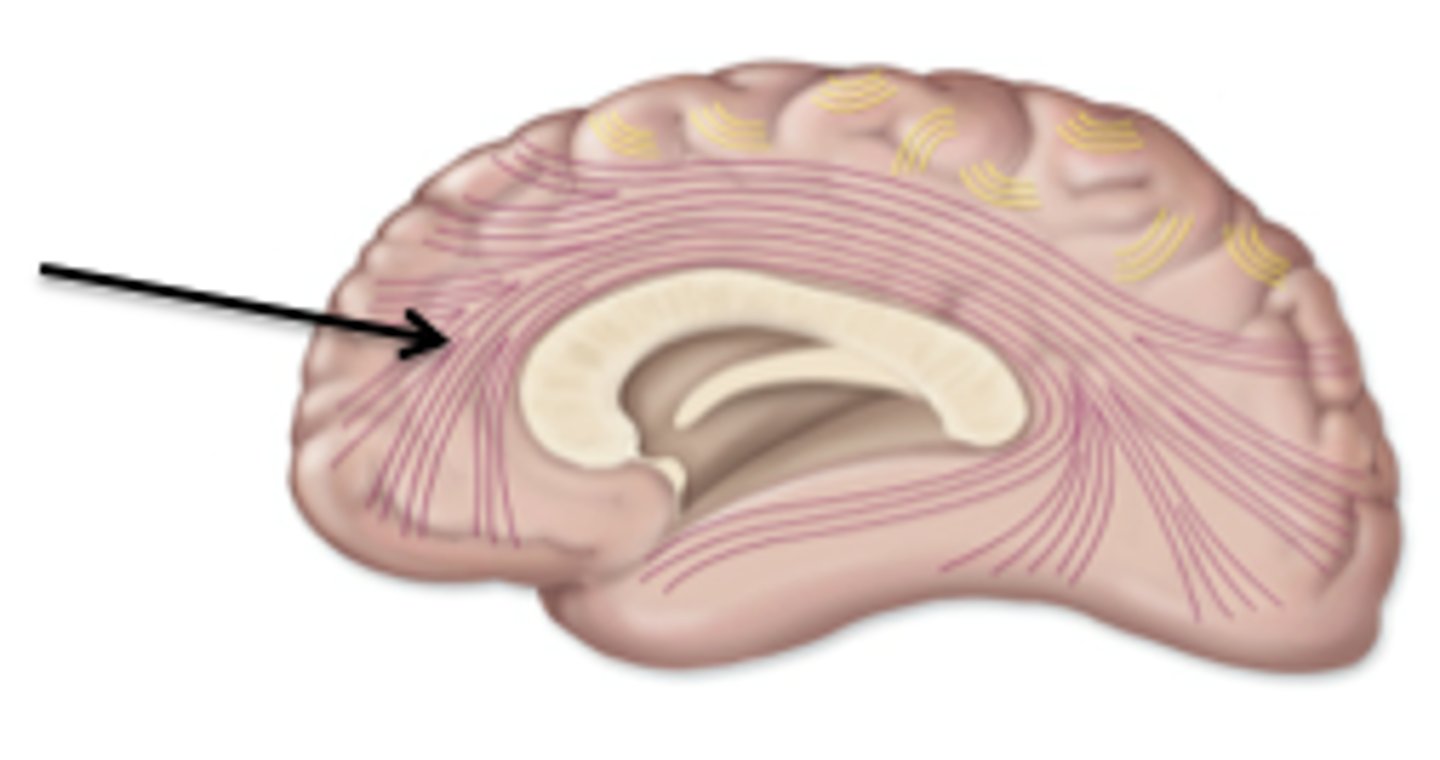

white matter

myelinated axons

Association tracts of white matter

conducts nerve impulses between cerebral gryri in the same hemisphere

commissural tracts of white matter

conducts nerve impulses one cerebral gyri to corresponding gyri in the other cerebral hemisphere.

projection tracts

conduct nerve impulses from cerebrum to lower parts of the CNS or from lower pars of the CNS to the cerebrum